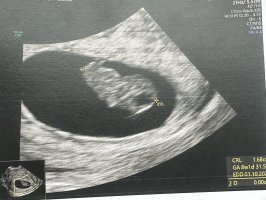

Så rart, vi har termin samme dag og jeg er 7+1. Min var 11 millimeter. Kanskje din er større? (Synes dette var interessant) Gratulerer så masse uansett <3Alt perfekt![]()

Målte tilsvarende 7+5, som er en dag lenger enn vi var (7+4)

12,7 millimeter her, og dette er IVF-baby, så vi vet på timen hvor gammel den erSå rart, vi har termin samme dag og jeg er 7+1. Min var 11 millimeter. Kanskje din er større? (Synes dette var interessant) Gratulerer så masse uansett <3

Så spennende! Fikk litt wow følelse av hvor presist det kan være. Veldig gøy også!12,7 millimeter her, og dette er IVF-baby, så vi vet på timen hvor gammel den er![]()

Her var lille økt fra 4 mm forrige tirsdag til 11 mm i dag12,7 millimeter her, og dette er IVF-baby, så vi vet på timen hvor gammel den er![]()

Så nydelig! Tenkte på deg når vi satt på de grønne stolene og ventetHer var lille økt fra 4 mm forrige tirsdag til 11 mm i dagJeg er 7+2 i dag og det stemte helt med IVF-datoen og målingen